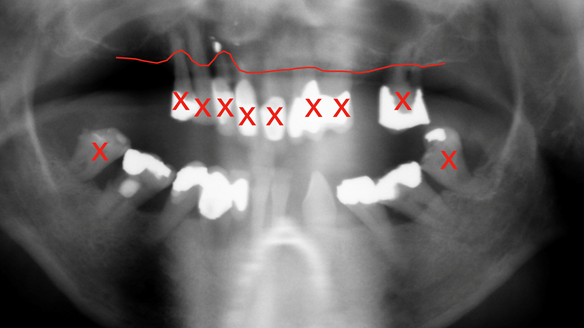

- The remaining natural upper natural teeth and lower back molars were heavily restored having generalised periodontitis stage 4 Grade C. Some of the teeth exhibited caries. The prognosis for these teeth ranged from dubious to hopeless.

- The upper and lower acrylic based partial dentures exhibited suboptimal extension of the flanges and saddles. They had poor retention, support, stability and tissue fit.